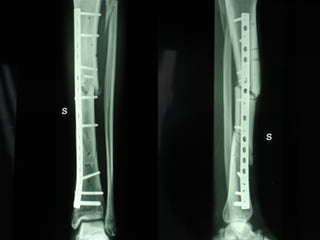

Dal Gennaio 2000 al Febbraio 2006 abbiamo trattato 167 fratture chiuse  con placca percutanea  in 164 pazienti :  27 lesioni diafisarie di gamba, 12 piloni tibiali ,  11 fratture prossimali di tibia, 36 fratture sovracondiloidee di femore, 17 fratture diafisarie di femore, 43 fratture metaepifisarie prossimali di omero, 21 diafisarie d’omero.  156 guarigioni 8 fallimenti

Dal Giugno 2002 al Dicembre 2004 abbiamo trattato 5 fratture esposte: 3 di tibia e 2 di ulna 5 guarigioni

I buoni risultati ottenuti dipendono da 5 punti fondamentali:   una accurata riduzione percutanea della frattura  precise vie di accesso  l’utilizzo della placca che consenta il più lungo braccio di leva possibile il pretensionamento della placca  una sintesi con un ridotto numero di viti

Precise vie di accesso

Placche lunghe e pretensionate

Placche lunghe e pretensionate Sintesi con un ridotto numero di viti